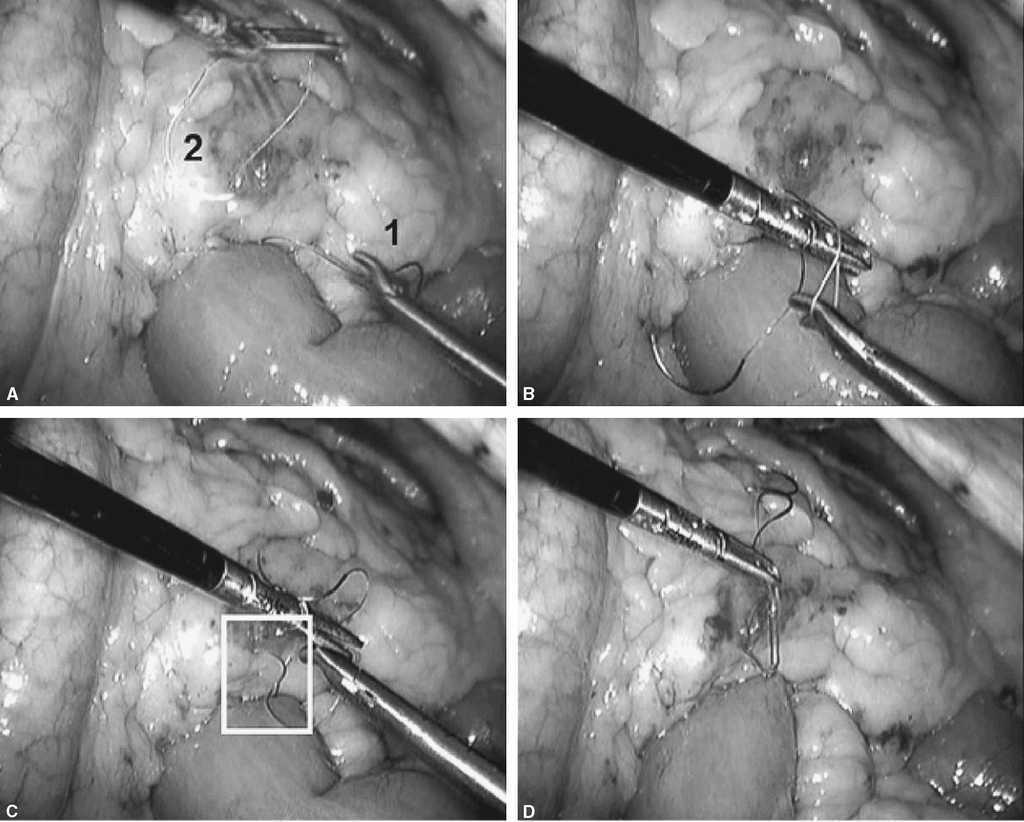

Fig. 5. A: en este momento tendremos 2 suturas con 2 agujas que parten del mismo punto. Una de las 2 suturas pasará por debajo del asa de Roux en su punto más craneal (flecha blanca) y la otra se quedará en el mismo sitio (lado izquierdo del asa de Roux). La flecha negra indica la yeyuno-yeyunostomía. B: se avanza el asa de Roux al orificio creado en el mesocolon con un grasper atraumático. C: identificamos fácilmente la sutura que pasamos previamente por debajo del asa Y de Roux. D: se observa las 2 suturas.

Fig. 6. El objetivo ahora es seguir con la sutura continua por ambos lados del asa Y de Roux cerrando el espacio de Petersen y ojal de mesocolon transverso haciendo una corbata. A: cómo se hace con la sutura 1 el cierre del meso en el lado izquierdo. B: es importante para este propósito coger la serosa intestinal y tejido graso del meso. C: en el cuadrado blanco se aprecia que la sutura avanza y coge serosa intestinal. D: una vez llegado a la mitad se deja la sutura y avanzaremos la sutura 2 desde el otro lado hacia la sutura 1.